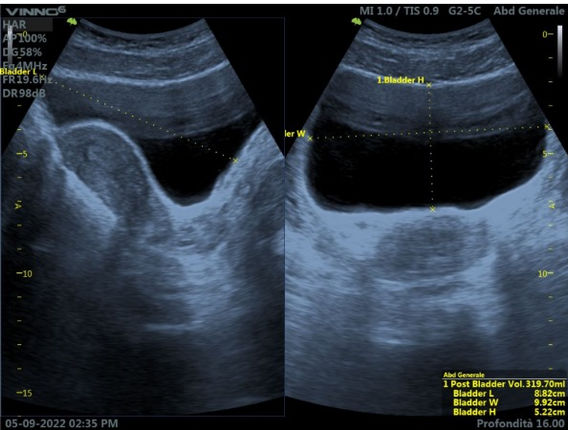

Dopo avere acquisito manualità e preso confidenza con lo studio del fegato è ora di fare conoscenza con gli altri organi addominali e sovrapubici.